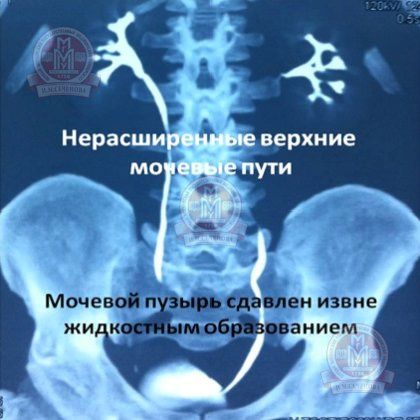

Малюнок № 9 (МСКТ). Нерасшіренние верхні сечові шляхи, сечовий міхур заповнений контрастом і здавлений ззовні рідинним утворенням.